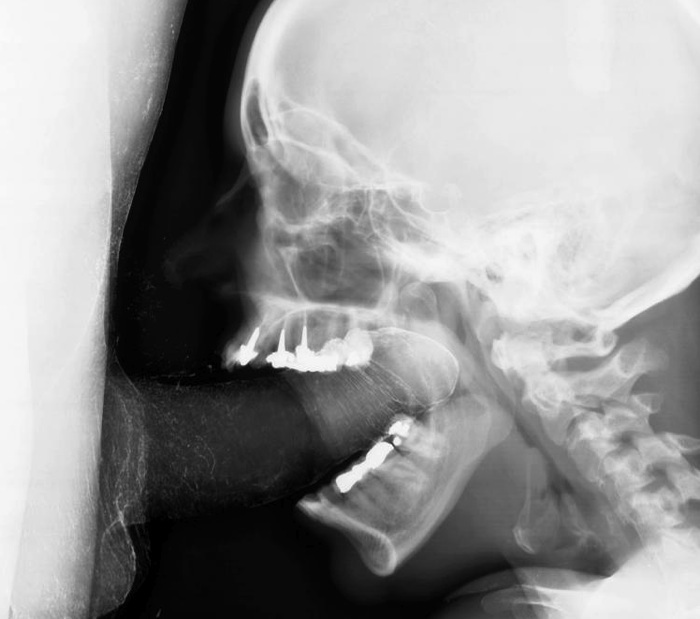

А что за дырка во лбу?Так должно быть или это след от трепанации?)

третий глаз открылся.

с помощью копья.

Я бы лучше спросил, что у неё с зубами 8-)

N'urk (09:59), он это или она еще надо подумать, а вот на счет дырки во лбу - так это пазухи у всех полов присутствуют, у этого персонажа еще и гайморит : )))))

почти на всех зубах пломбы, некоторые с рутканалами :)